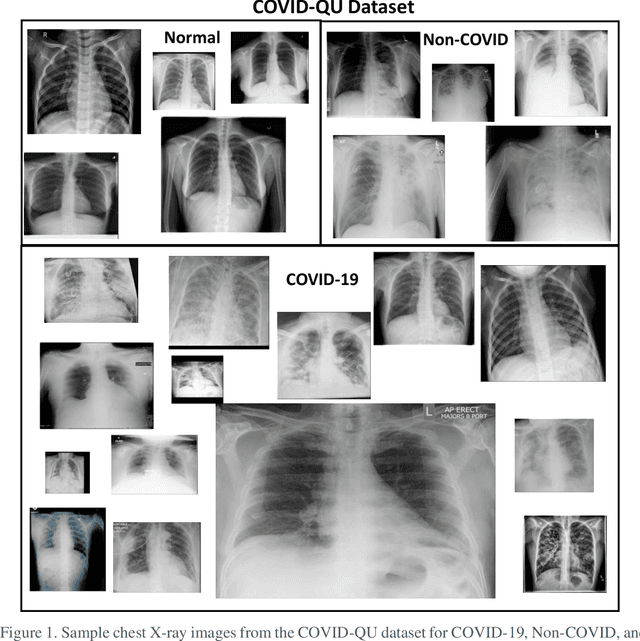

Abstract:Coronavirus disease 2019 (COVID-19) has been the main agenda of the whole world, since it came into sight in December 2019 as it has significantly affected the world economy and healthcare system. Given the effects of COVID-19 on pulmonary tissues, chest radiographic imaging has become a necessity for screening and monitoring the disease. Numerous studies have proposed Deep Learning approaches for the automatic diagnosis of COVID-19. Although these methods achieved astonishing performance in detection, they have used limited chest X-ray (CXR) repositories for evaluation, usually with a few hundred COVID-19 CXR images only. Thus, such data scarcity prevents reliable evaluation with the potential of overfitting. In addition, most studies showed no or limited capability in infection localization and severity grading of COVID-19 pneumonia. In this study, we address this urgent need by proposing a systematic and unified approach for lung segmentation and COVID-19 localization with infection quantification from CXR images. To accomplish this, we have constructed the largest benchmark dataset with 33,920 CXR images, including 11,956 COVID-19 samples, where the annotation of ground-truth lung segmentation masks is performed on CXRs by a novel human-machine collaborative approach. An extensive set of experiments was performed using the state-of-the-art segmentation networks, U-Net, U-Net++, and Feature Pyramid Networks (FPN). The developed network, after an extensive iterative process, reached a superior performance for lung region segmentation with Intersection over Union (IoU) of 96.11% and Dice Similarity Coefficient (DSC) of 97.99%. Furthermore, COVID-19 infections of various shapes and types were reliably localized with 83.05% IoU and 88.21% DSC. Finally, the proposed approach has achieved an outstanding COVID-19 detection performance with both sensitivity and specificity values above 99%.